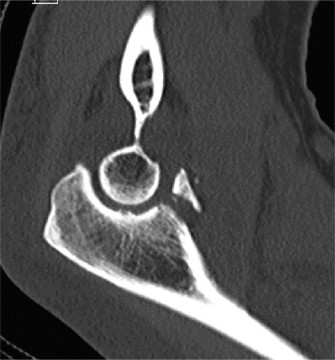

After evaluating the MRI, the patient is diagnosed with a complete rupture of the pectoralis major tendon (Fig. 2–79). What is the recommended first step in management?

Figure 2–79